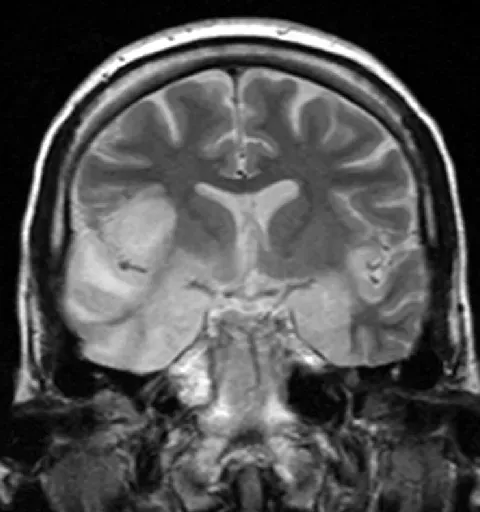

The Brain on Fire: Why Some Immune Systems Suddenly Attack the Mind

One of the most unsettling modern mysteries in medicine is autoimmune encephalitis, sometimes called the “brain on fire” syndrome. In these cases, a person who seemed perfectly healthy can suddenly become paranoid, hallucinate, have seizures, or slip into catatonia in a matter of days or weeks. Doctors now know that, in some patients, antibodies are attacking receptors on brain cells – especially receptors for glutamate and other neurotransmitters – but they still do not fully understand what triggers this immune rebellion. In many documented cases, a tumor or infection seems to set off the chaos, but in a large share of patients, no clear cause is ever found. The terrifying part is that the condition can initially look like a psychiatric crisis, so people may be misdiagnosed with schizophrenia or bipolar disorder instead of a treatable immune disease.

When caught early, high‑dose steroids, immune‑suppressing drugs, and even blood‑filtering treatments can bring people back from the brink, sometimes almost completely. Yet others are left with lasting memory gaps, personality changes, or epileptic seizures even after the antibodies have dropped. Why one person’s immune system turns on their brain at twenty and another’s never does remains an open question. Researchers suspect a mix of subtle genetic risk, environmental triggers, and viral exposures that may have happened years before symptoms. That blend of science and uncertainty makes every new case both hopeful, because treatments exist, and haunting, because the underlying switch that flips from normal to attack mode is still invisible.